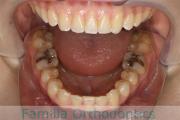

No.22V-104

- 主な症状:

- 側方偏位

- その他の症状:

- 叢生

- 年齢:

- 19歳

- 性別:

- 女性

- 主な使用装置:

- FEA

- 治療にかかった費用:

- 90万円

歯並びを綺麗にしたいということで来院されました。叢生(でこぼこ、凹凸、ガタガタ)と上下顎前突のため、上下左右から小臼歯を抜歯の上で、歯科矯正用アンカースクリューを併用したマルチブラケット法を行いました。約2年半、30回の通院が必要でした。

上下とも叢生がありますので、後戻りのリスクがあります。